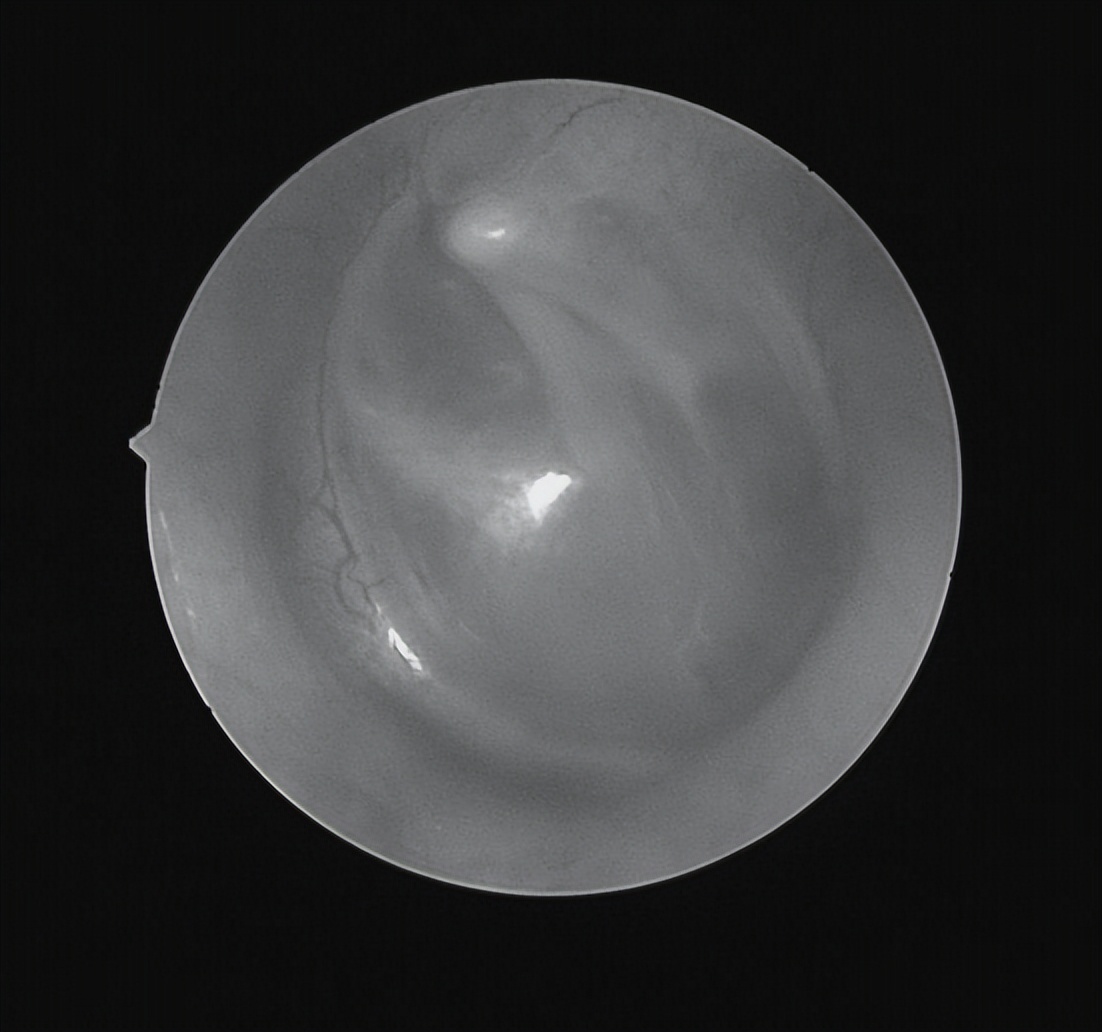

耳内镜检查

双耳鼓膜完整,右侧鼓膜内陷明显,右侧鼓室可见积液